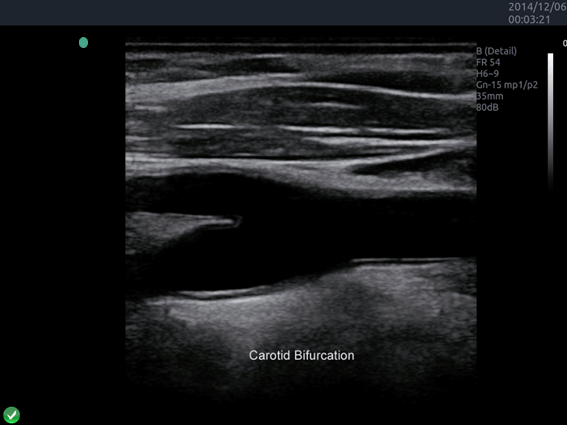

Invictus E5

O ultrassom Invictus E5 apresenta um design moderno e exclusivo, com perfeito fluxo de trabalho e interface intuitiva.

Dentre suas características inovadoras, podemos destacar a tela em LCD com rotação de 60° para ambos os lados, para otimização da visualização durante os exames; tela touch screen com menu totalmente customizável; painel de controle totalmente selado para facilitar limpeza e desinfecção da superfície, o que o torna referência para ser utilizado principalmente em Centro Cirúrgico.

Apresenta excelente qualidade de imagem, trabalho otimizado através de presets pré-determinados, sensibilidade e eficiência em aplicações de Point of Care e portanto, uma perfeita relação custo benefício.